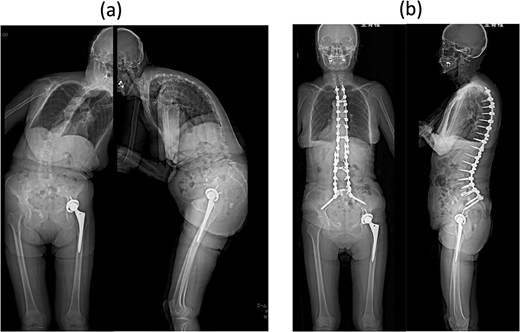

An 80-year-old woman presented to our department complaining of back and leg pains, as well as postural imbalance. She could stand continuously for 10 min and experienced intermittent claudication after walking 300 m. She was diagnosed with kyphoscoliosis and lumbar spinal canal stenosis and subsequently underwent corrective spinal fusion surgery from T4 to the ilium (Fig. 1).

Standing whole-spine anteroposterior and lateral radiographs (a) preoperative and (b) after the first surgery.